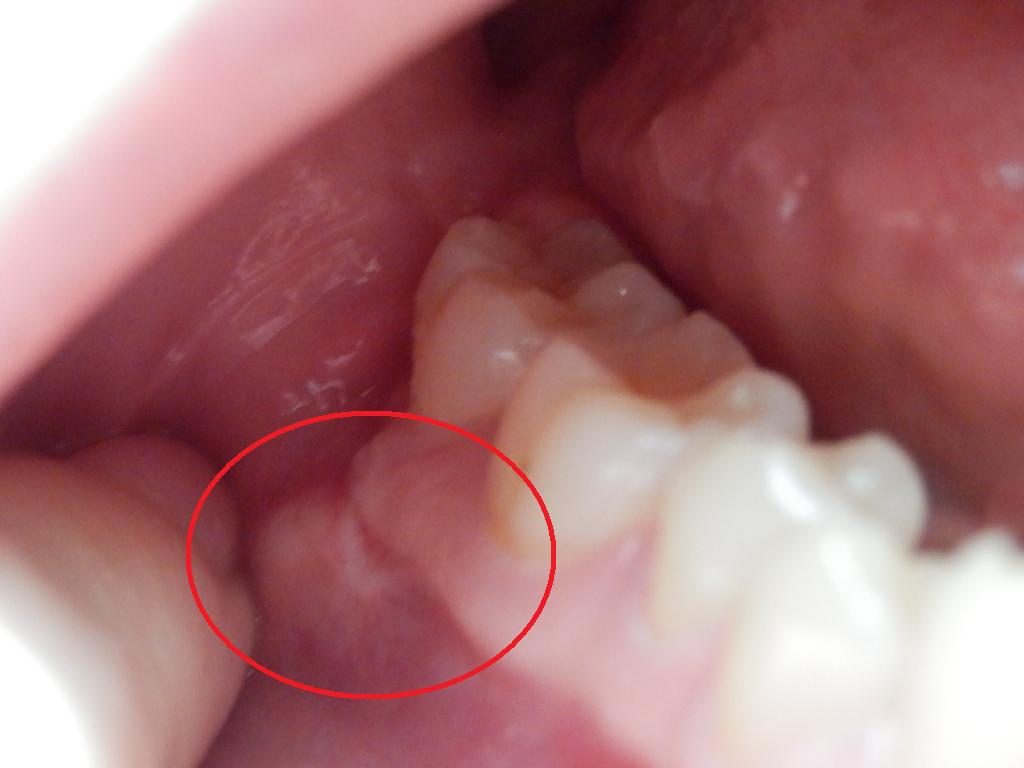

La boule blanche bb inox la petanque de precision J ai pus assiste au championnat africain d ailleur remporter par les,marocain ou les joueurs on trouve un tres grand plaisir avec la bouleblanche equilibre a la perfection au 2centiem de milimetre pres ce qui merite 5 etoiles A bientot Unknown a di La Boule Blanche Carbone En Italie, les marques Unibloc et Futura fabriquent leurs1606 · Camilia® est un médicament homéopathique utilisé pour soulager la douleur, l'agitation, l'irritabilité et la diarrhée liées à la poussée dentaire Camilia est élaboré à base d'eau stérile Ce médicament est sans sucre, sans colorant, sans benzocaïne ni agent de conservation Disponible en 15 et 30 dosesBonjour je sent une bosse au toucher sur ma gencive pres de ma dent arriere cela me fait malsuite a une visite chez le dentiste il ma fait faire une plaque occlusale car je souffre de fibromyalgie chronique qui me cause un trouble de larticulation temporomandibulairele dentiste ma fait une radiographie de la dent mais rien pas de carie mais il ne voit pas la bosse mais moi au toucher je

· Alors qu'il est en pleine découverte du monde, difficile pour un enfant de moins de 6 ans d'échapper aux chutes Apprentissage de la marcheLes dents permanentes apparaissent entre ± 6 et 13 ans et comprennent · Une bosse, un gonflement ou une enflure de la gencive sont des réactions révélant un problème qui affecte les dents ou l'os sur lequel cellesci sont implantées Il s'agit souvent d'un signe d'infection

2221 · Une boule blanche sur la gencive peut être due à un abcès dentaire, infection bactérienne pouvant entraîner une douleur ou non Les dents réagissent normalement au froid et au chaud Site de l'Assurance Maladie Amelifr AVERTISSEMENT Tout le contenu de ce site est fourni à titre d'information complémentaire uniquement et ne remplace en aucun cas un conseil · Bébé a les gencives gonflées que faire La douleur est souvent importante et il est donc normal de se demander, si le bébé a des gencives gonflées, que faire C'est ceMais il a fait quand même ses dents très tôt vers 3 4 mois également ,ah il bavait énormément à sa naissanceIl a fait toutes ses dents très vite ce qui lui a permis de manger des morceaux plus facilement dc pas d'inquiétude

· Boule blanche et dure sur la gencive Publié dans Les mamans maryjo le 19 octobre 09 à 11 h 05 min #54 J'ai demandé il y a quelques jours si quelqu'un savait ce que pouvais être cette boule dure et blanche que "Maëlys" avait sur la gencive · "Il arrive occasionnellement qu'un bébé commence à faire ses dents pendant le premier mois, mais il est plus probable que les bosses sur les gencives de votre nouveauné sont des kystes buccaux – des petites papules remplies de fluide Ces kystes sont plutôt communs chez les nouveaunés et ne font pas de mal à l'enfant · Dans le premier cas, c'est la gencive qui est infectée, sensible et douloureuse, avec la formation de boules blanches contenant du pus

· Les boules blanches sur la gencive Une boule blanche sur la gencive peut être due à un abcès dentaire , infection bactérienne pouvant entraîner une douleur ou non Ce type d'infection se situe en périphérie de la racine d'une dent et génère dans les premiers temps la formation d'un kyste infectieux (comme évoqué plus haut), avec collection de liquide inflammatoire pour gérerDans quel ordre apparaissent ces petites pointes blanches ?1606 · Moi je reviens de chez le pédiatre pour la visite des 4 mois de ma pepette, qui, elle aussi avait une pointe blanche sur la gencive inférieure je pense donc à sa première dent, mais tout à disparu, Le péditre m'as dit qu'il s'agissait en fait de perle gingivale du cartilage qui sort des gencives, ça arrive frequemment

Boule Sur La Gencive Cmd Balexert

Enflure Ou Bosse Sur La Gencive Bucco Guide Des Soins Trouver Le Bon Dentiste Selon Vos Besoins